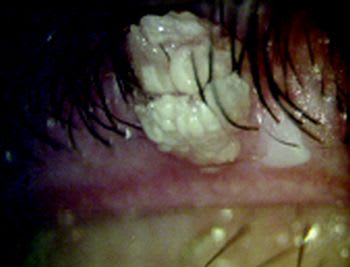

The white lesion at the margin of this patient's eyelid is a viral wart treated moments earlier with dichloroacetic acid. The acid destroys the lesion and permits growth of normal epithelium thereafter.

While eyelid warts are often asymptomatic, some individuals experience itching and may present with a follicular conjunctivitis. Treatment may be accomplished through excision with scissors, focal treatment with freezing or with chemical cautery. Others have reported using argon laser to destroy these lesions. Our experience with chemical cautery has been excellent with minimal recurrence of the lesions after treatment.